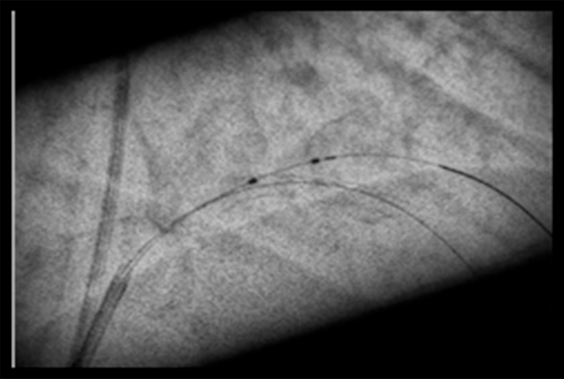

StentBoost Live

Azurion(아주리온)은 최신 인터벤션 소프트웨어가 탑재되어 있어 심혈관중재시술 시 더욱 용이하게 환자를 시술할 수 있도록 해준다. 최근 도입된 다이내믹 코로너리 로드맵(Dynamic Coronary Roadmap)과 스텐트부스트 라이브 (StentBoost Live)는 복잡하고 어려운 심장 혈관 및 심장 구조 질환의 치료에 성공적인 시술을 할 수 있도록 도와준다. 두 기술 모두 까다로운 심혈관중재시술 시 실시간 레퍼런스로 활용할 수 있어, 시술 시간의 단축, 방사선 피폭 및 조영제 사용량을 최소화할 수 있다.